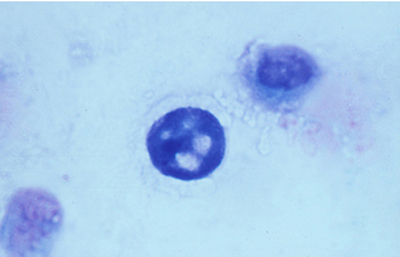

Coloración de Giemsa

En un frasco de Copli colocar 10 ml de la solución del colorante de Giemsa con 90 ml de un buffer fosfato 1/15 M y pH 6.8. Colorear el extendido fijado por 20 minutos. Lavar en agua corriente y dejar secar al aire. Aclarar en xileno por 5 minutos y montar con un medio de resina.

Los quistes Acanthamoebas midien de 10 a 16 µm de diametro, con capsula de forma circular o poligonal, a veces con angulaciones y ondulaciones, (Figura 41) teñido densamente azul oscuro. Membrana plasmática con tinción más tenue, concéntica, o retraida o colapsada asimétricamente. Coloración variable del citoplasma. (Figura 42, 43, 44 y 45)

Fig. 41 Giemsa. Original x400

Fig. 42 Giemsa. Original x200

Fig. 43 Giemsa. Original x160

Fig. 44 Giemsa. Original x160

Fig. 45 Giemsa. Original x200

Fig. 46 Giemsa. Original x160

En ocasiones cariosoma central prominente (en ojo de buey) (Figura 46) y quistes claros, vacios, compuestos sólo por la doble pared del quiste y membrana plasmática.

Cuando los quistes se localizan en el epitelio o en detritus colágenos y fibrinoides, el ectoquiste puede ser refringente, transparente o tenuemente azulado y el tendoquiste densamente coloreado de azul por el Giemsa. (Figura 47)

Los trofozoitos son más difíciles de visualizar, siendo mayores que los quistes. En preparaciones fijadas, son de forma circular, con pequeño núcleo y citoplasma con numerosos organelos y vacuolas (Figura 48)